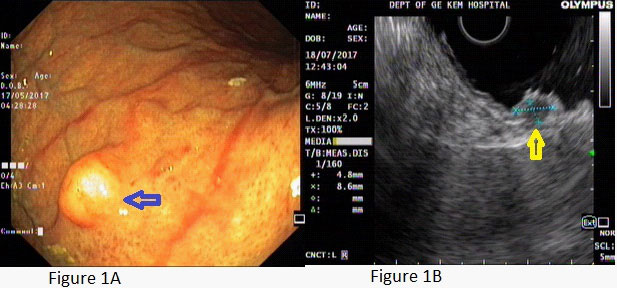

A young female presented with postprandial fullness and bloating, sensation of something sticking inside throat. There was no history of dysphasia, heartburn, gastrointestinal bleed, weight loss and no significant medical or surgical illness. Her physical and biochemical examination was normal. Upper gastrointestinal endoscopy showed normal esophagus with the presence of a single submucosal yellowish white elevated lesion, seen in the body of the stomach, measuring approximately 1 X 0.5 cm with normal overlying mucosa (Figure1A). This was followed by endoscopic ultrasonography (EUS) which revealed homogenous hypoechoic mass arising from submucosa of the stomach (Figure 1B). Biopsy was done and histology showed scanty tissue with normal stomach mucosa and submucosa showed a hyalinised area with presence of few scattered polygonal cells (Figure 2A). Hence an Immunohistochemistry was performed for S100 and CD68 which turned out to be strongly positive (Figure 4A and 4B). Thus, a diagnosis of GCT was made. Subsequently an endoscopic resection of the tumor was done. On gross, the resected nodule measured 1 X 0.5 X 0.5 cm and was yellowish white on cut surface. Histology showed normal gastric mucosa with underlying submucosa showing an unencapsulated mass composed of short fascicle polygonal to fusiform cells with abundant granular eosinophilic cytoplasm, positive on PAS and plump oval nuclei (Figure 3A and 3B). Mitotic figures and necrosis were not seen. This confirmed the diagnosis of GCT. On follow up patient got relieved of symptoms after resection and colonoscopy done later confirmed absence of GCT at any other site.

Figure 1: Showing a nodular lesion in submucosa with overlying normal gastric mucosa in UGI scopy (blue arrow in Figure 1A) and in EUS (yellow arrow in Figure 1B).